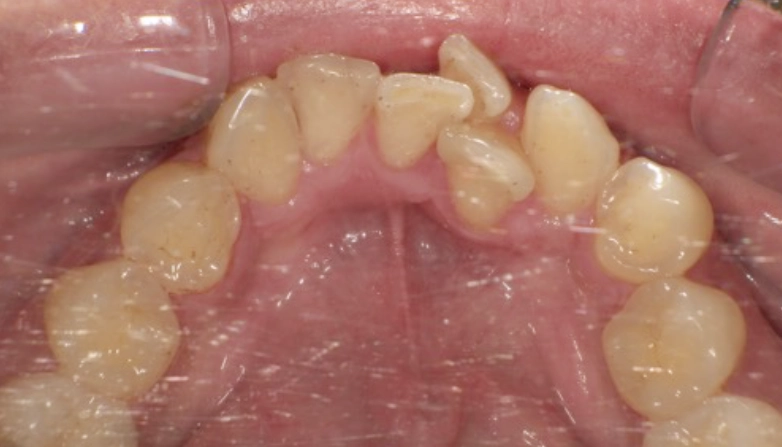

症例2

before

after

| 主 訴 | 着色を落としたい |

| 治療期間 | 通院 1回 |

| 治 療 費 | 1回 7,700〜11,000円(税込) |

| 治療内容 | PMTC |

| 治療のリスク | 歯自体の色を白くすることはできない。 しばらくすると再び着色することがある。 |